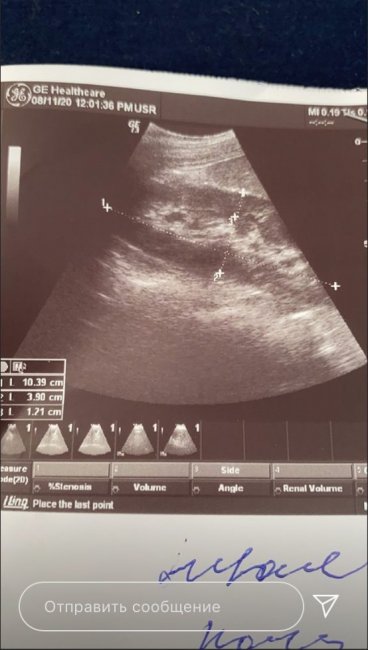

Во время отпуска в Дагестане 20-летней блогерше стало плохо. Девушку моментально доставили в больницу и в итоге поставили неутешительный диагноз. У Дианы обнаружили камни в желчном пузыре, и врачи сообщили, что ей придется удалить весь орган.

«Весь желчный пузырь в камнях. Размеры от четырех миллиметров до одного сантиметра. Убрать камни не получится. Скоро операция, придется удалять желчный пузырь навсегда. В противном случае может быть панкреатит и абсцесс. Как реагировать, не знаю. Морально тяжело»,

– написала Дина в своем профиле в Instagram.